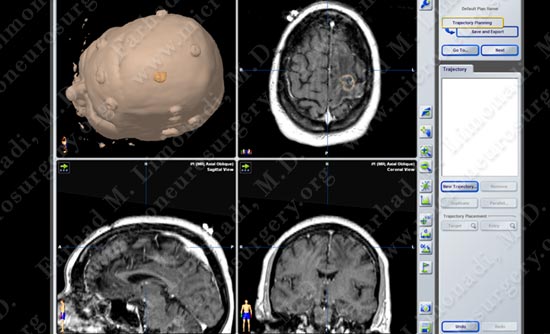

Imaging

MRI scan of patient's brain shows a tumor within the motor cortex gyrus.

Computer navigation and stereotaxy utilized to map and localize the tumor (outlined in yellow) during surgery.